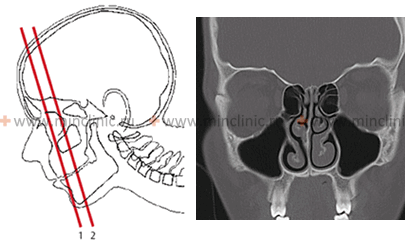

•СКТ головы с контрастированием (включая оценку инвазии в головной мозг) и шеи (до биопсии, шаг 3 мм)

Всех пациентов с подозрением на рак полости носа и придаточных пазух направляют на обзорную рентгенографию соответствующей области. При возможности проводят рентгенографию с использованием контрастного вещества, КТ и МРТ. При подозрении на прорастание рака околоносовых пазух в полость черепа назначают рентгенографию черепа. В некоторых случаях осуществляют диагностическую гайморотомию. Для выявления гематогенных метастазов выполняют рентгенографию грудной клетки и УЗИ брюшной полости.

- КТ придаточных пазух носа. Компьютерная томография дает наиболее четкое изображение образования: форму, контуры, размеры и локализацию. По результатам рентгенологической диагностики определяют вид остеомы: периферическая краевая, наружная угловая, опухоль задней стенки, новообразование из носового отростка лобной кости.

В распознавании опухолей носа существенное значение имеет специальное обследование больного оториноларингологом (риноскопия и др.), офтальмологом (исследование полей и остроты зрения, глазного дна и др.) и рентгенологом (рентгенологическое исследование, томография и др.). В ряде случаев на рентгенограмме видно, в какую сторону отдавлена сохранившаяся часть костной стенки, отделяющая полость носа от глазницы, что помогает определить направление роста опухоли (из глазницы в полость носа или наоборот). Компьютерная томография (КТ) или магниторезонансная томография (МРТ) дополняет полученные данные. Прогноз при прорастании опухоли в орбиту всегда серьезный.